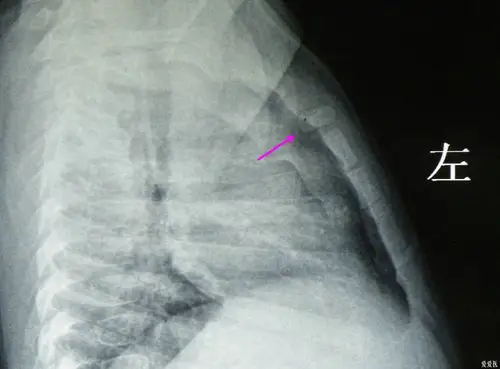

胸骨发育异常